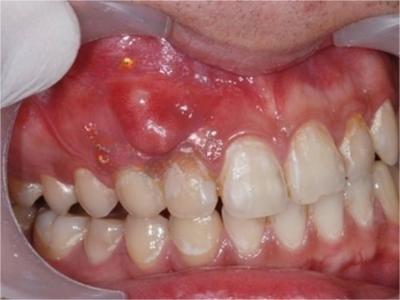

根尖囊肿是成牙组织囊肿中最常见者,多发生在上列切牙、尖牙或磨牙等牙根的唇面。由于根尖肉芽肿、慢性炎症的刺激,引起牙周膜内的上皮残余增生。增生的上皮团中央发生变性与液化,周围组织液不断渗出,逐渐形成囊肿,故亦可称根尖周囊肿。

根尖囊肿生长缓慢,病人多无自觉症状。口腔检查可见患牙有龋损或其他非龋性牙体病,或牙冠变色失去光泽。叩诊可有不适感,温度测验患牙无反应。囊肿大小不等,小囊肿不易被发现。囊肿发展较大时,可见根尖部隆起,扪诊时有乒乓球感,这是由于囊肿外围只有一层极薄的骨板存在。大囊肿还可压迫牙根,使邻牙移位。

根尖囊肿可由慢性根尖周肉芽肿或慢性根尖周脓肿等发展而来。因牙根感染、牙髓坏死,进而根尖周形成肉芽肿或脓肿,随后上皮细胞长入其内作为衬里形成囊肿内膜,病牙根尖突入囊肿腔内。增生的上皮团中央发生变性与液化,周围组织液不断渗出,逐渐形成根尖囊肿。